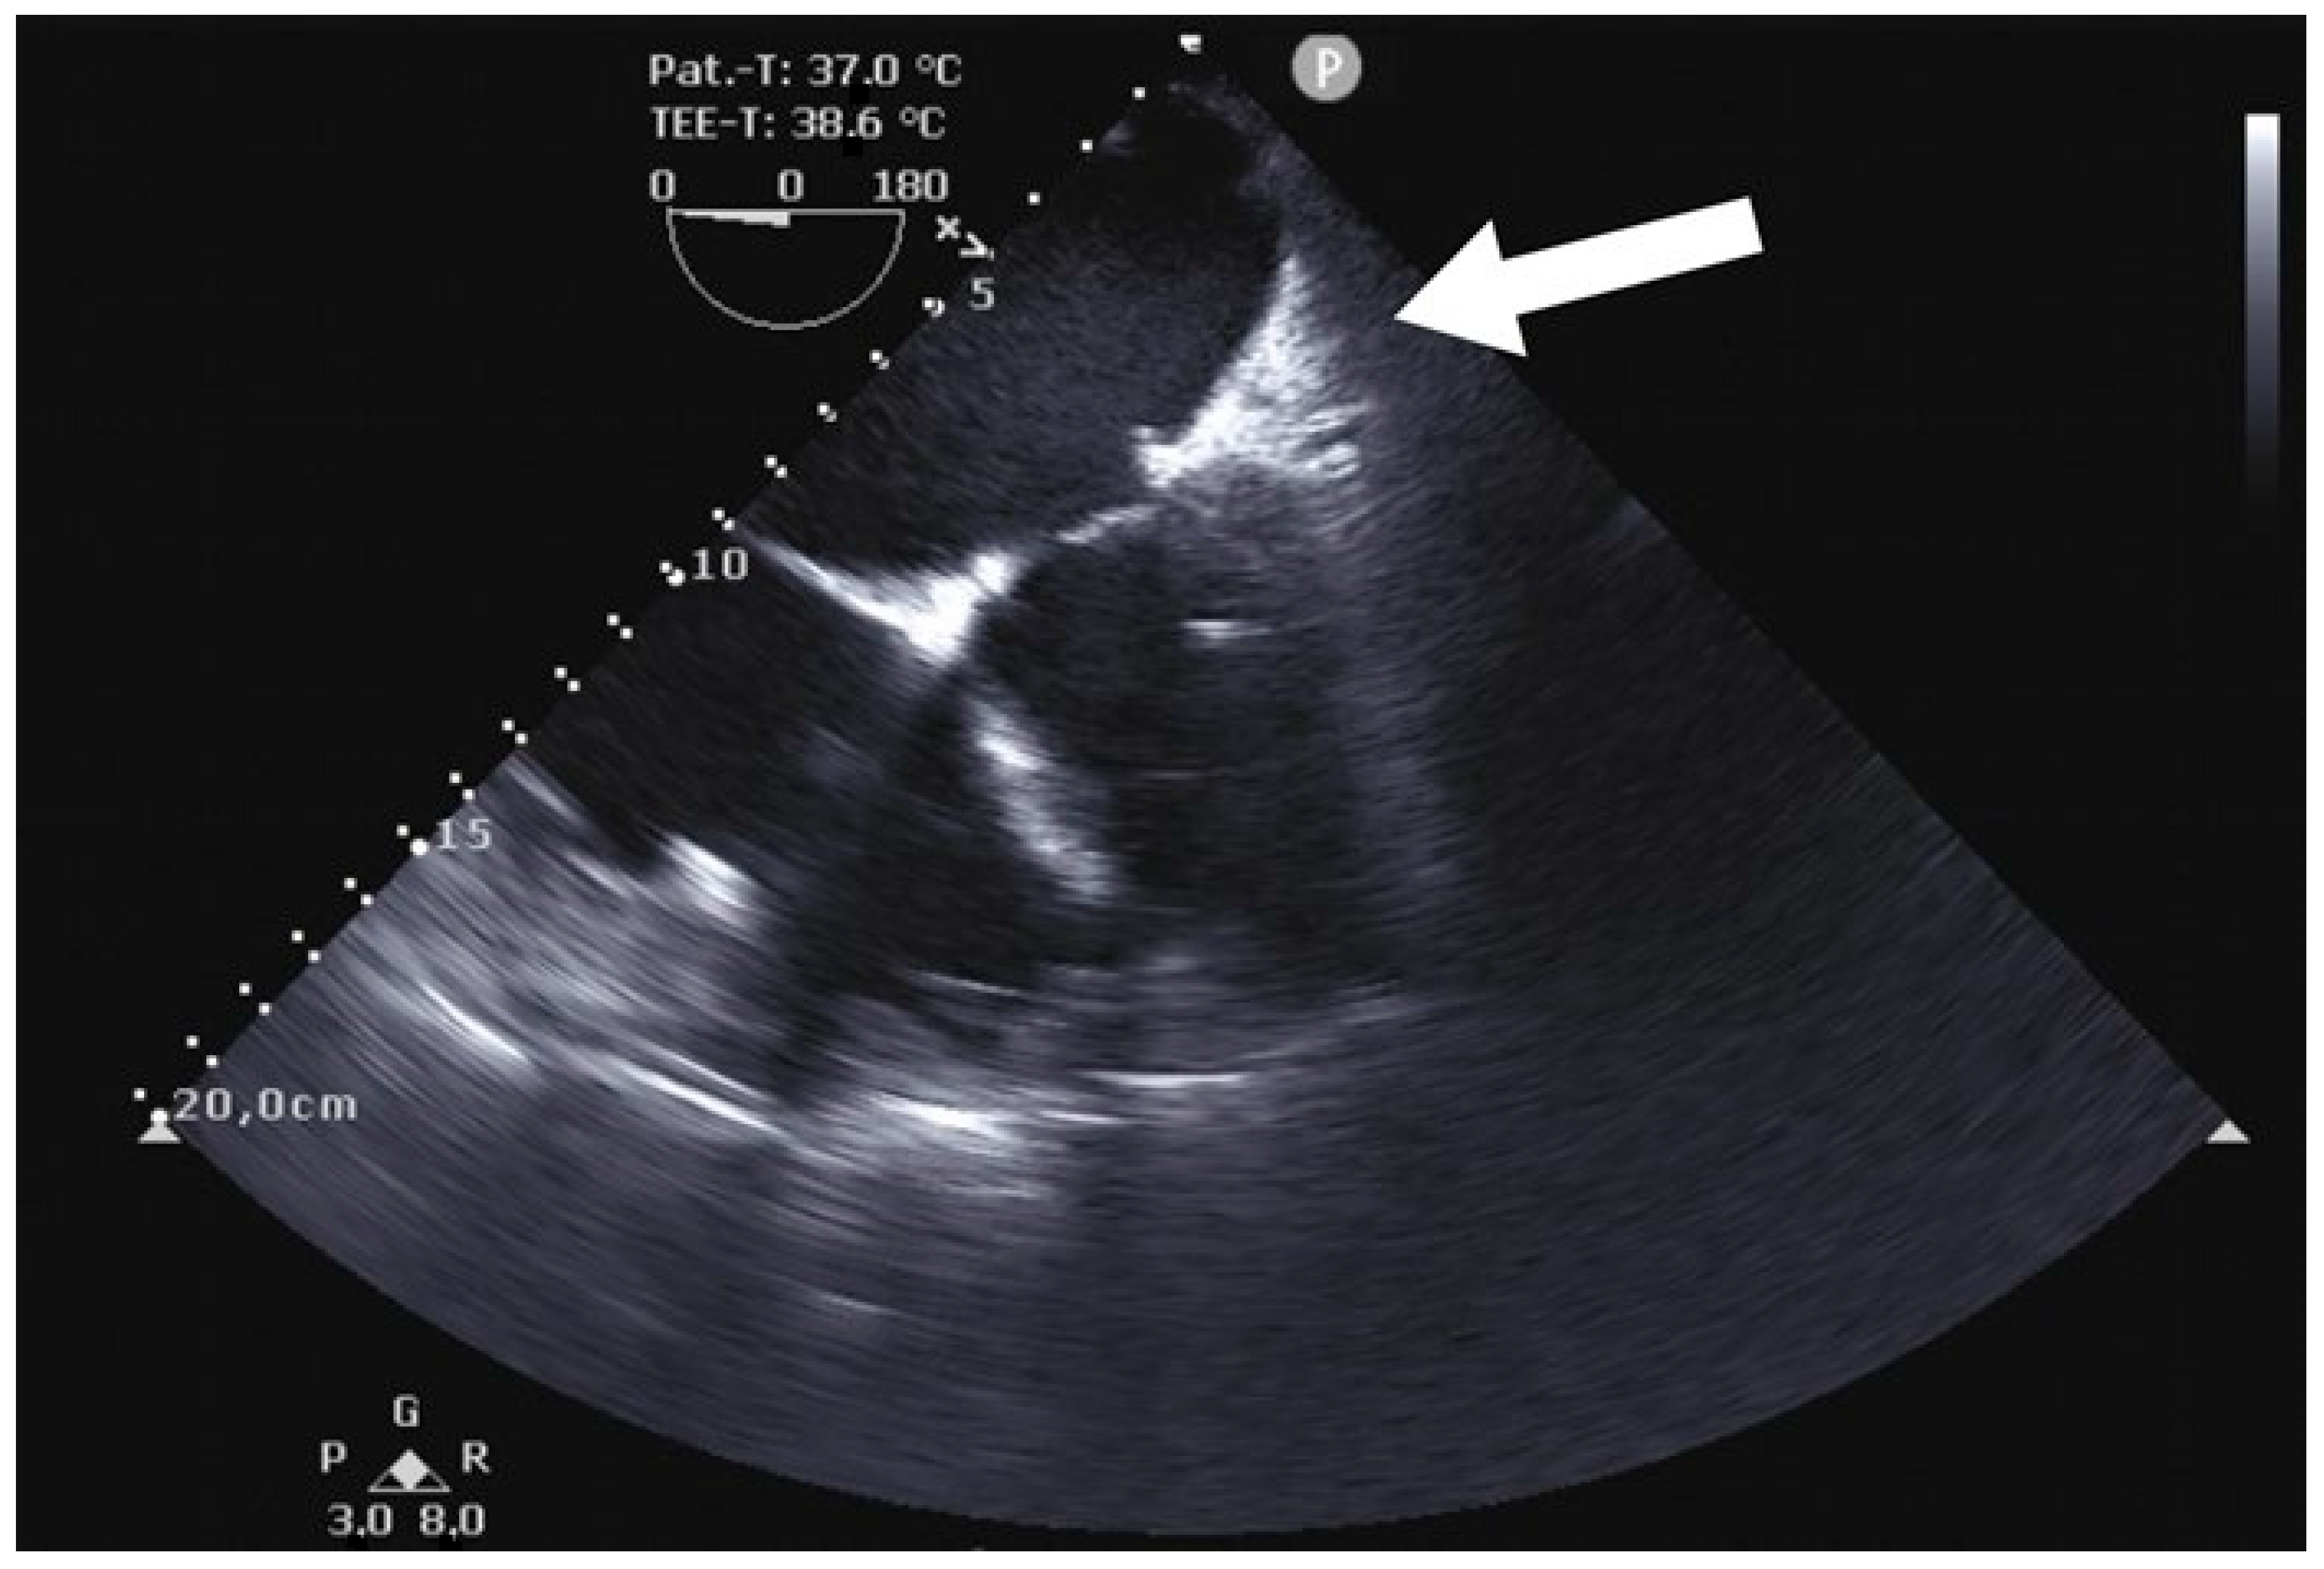

Using the AtriCure® (AtriCure, Mason, OH, USA) measuring device, the LAA base size was measured. After bending the AtriClip-Pro® (AtriCure, Mason, OH, USA) device, the clip was anteriorly passed over the LAA apex, gently compressing the great arteries and exposing the LAA. With a beating heart, the Atriclip-Pro® (AtriCure, Mason, OH, USA) was adequately placed under TEE guidance (Figure 4 and Figure 5), and the device was released after the confirmation of LAA closure (Figure 6 and Figure 7; Supplementary Video S1).

Figure 7. Postoperative transesophageal echocardiography showing the complete occlusion of LAA after correct placement of the AtriClip-Pro® (AtriCure, Mason, OH, USA) device (P: Pointer on ultrasound transducer).